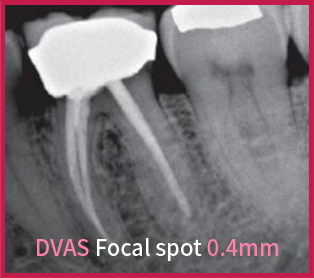

KRISTÁLYTISZTA KÉP

A 0,4 mm-es fókuszpont rendkívül éles, tiszta képet biztosít a fogorvosok számára.